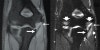

MRI : 팔꿈치 내측측부인대 파열(Ulnar collateral ligament tear)